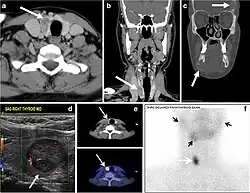

Fig. 4. A 45-year-old male patient presented with anterior mediastinal metastatic PTC lesions and occult primary on imaging. Histopathology examination of the resected thyroid gland revealed micro-foci of PTC; the largest, in the isthmus, measured 4 mm. a transverse greyscale ultrasound of the thyroid demonstrates homogeneous gland with normal echogenicity and size. No focal lesion or micro-calcifications. b Non-enhanced CT scan obtained as part of PET/CT examination shows a heterogeneous, large, relatively dense anterior mediastinal mass (white arrow) with peripheral calcification (arrowheads). Thyroid gland has normal CT appearance with no abnormal FDG uptake (not shown).[1] -

Fig. 6. A 61-year-old female patient with locally aggressive PTC. an Enhanced axial CT scan of the neck demonstrates a heterogeneous infiltrative thyroid mass. This mass diffusely involves the entire gland and circumferentially encases the trachea with involvement of bilateral tracheoesophageal grooves (white arrows). b, c Additional axial cranial images show right cricoid cartilage destruction (black arrows in b), right thyroid cartilage destruction (black arrow in c), right vocal cord paralysis (white arrows in b), and bilateral cervical lymphadenopathy (arrowheads).[1]